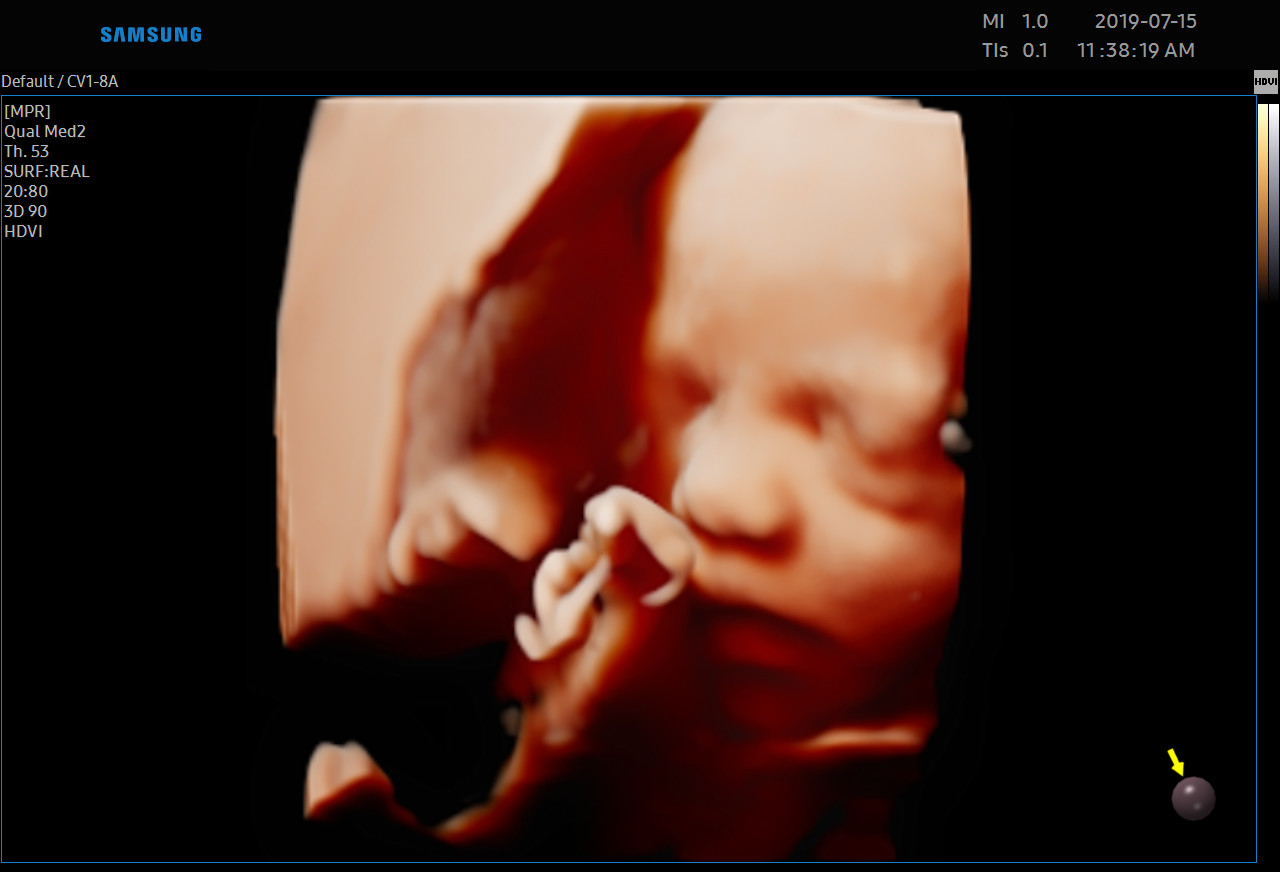

Każdą kobietę w ciąży otaczamy kompleksową opieką, czuwając nad jej zdrowiem oraz prawidłowym rozwojem płodu. Podczas regularnych wizyt, zlecamy odpowiednie badania laboratoryjne. Korzystając z najnowszej generacji aparatu USG, przeprowadzamy bardzo dokładną diagnostykę obrazową – łącznie z USG 3D/4D płodu.